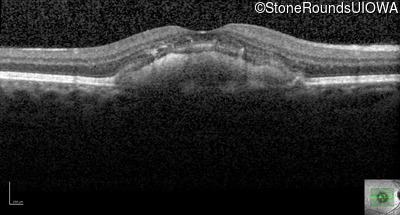

Age at visit: 53 years

Age at visit: 57 years

Diagnosis & molecular findings

Disease Gene Allele 1 variant(s) Allele 2 variant(s) Inheritance mode

Pattern Dystrophy PRPH2 Gly167Asp GGC>GAC   AD